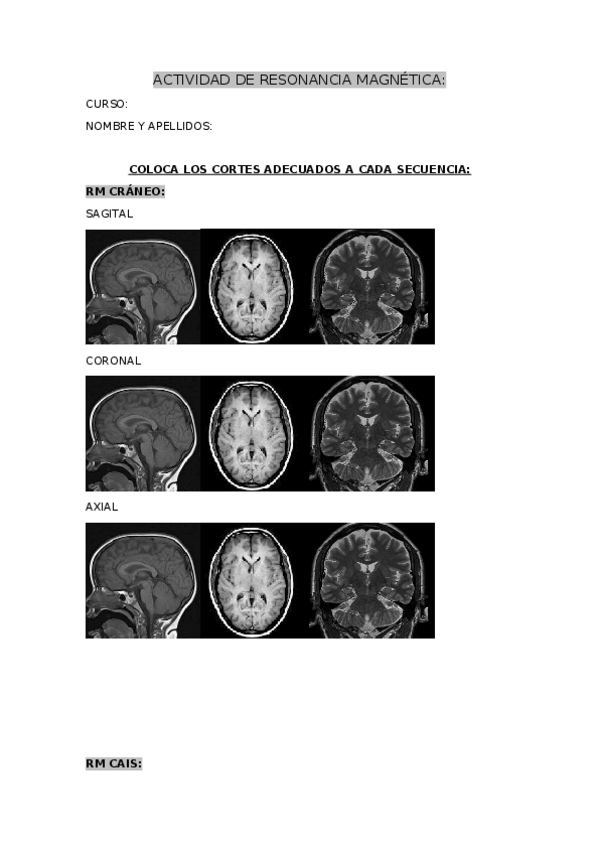

He publicado nuevos apuntes de Técnicas de Imagen por Resonancia Magnética: EXAMEN-RESONANCIA-MAGNETICA.docx

word